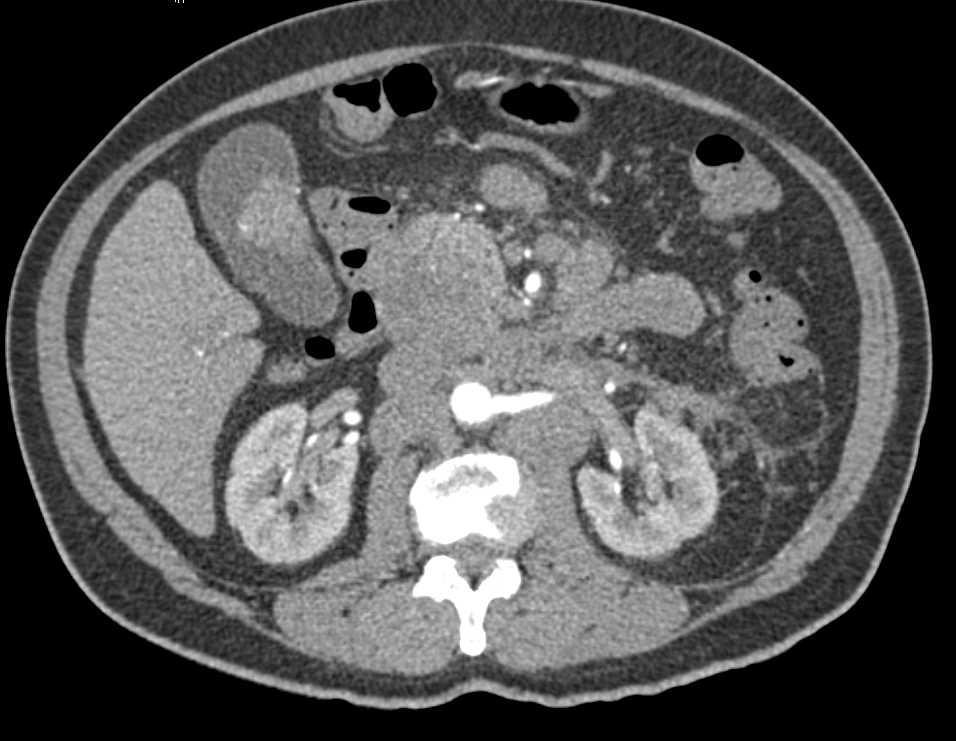

Small Bowel Enteritis